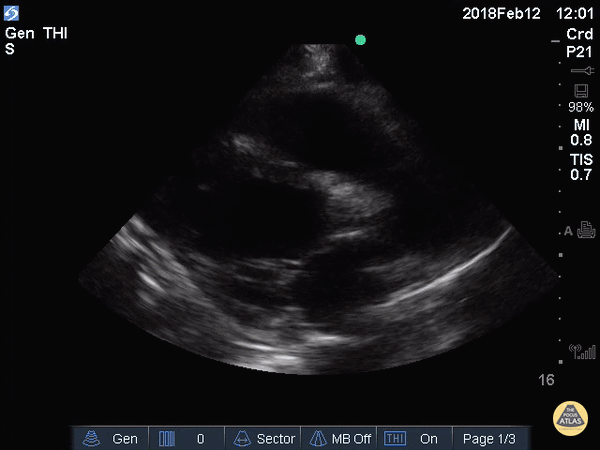

Die gezeigten Sono-Befunde wurden im realen Fall nicht präklinisch erhoben, sondern erst innerklinisch gesichert. Präklinisch war damals kein Sono-Geät verfügbar. Zu NERDfall-Zwecken gibt es die Bilder jetzt schon. Da im Original nicht vorliegend, wurden äquivalente Befunde von https://www.thepocusatlas.com gewählt.

Die Bilder zeigen also den aktuellen Zustand der Patientin. Bis auf die Sono-Befunde ist die Situation unverändert zu Zusatzinfo 1.

Parasternal lange Achse (Die hier gezeigte massiv reduzierte LV-Pumpfunktion war im realen Fall vermutlich etwas weniger ausgeprägt)